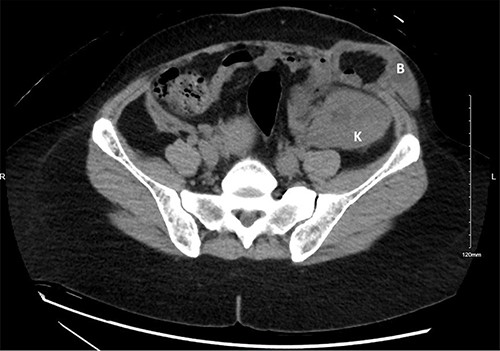

A 41-year-old female teacher G4P2 post second-time kidney transplantation presented to the hospital for her third elective CS at full term. The patient’s first kidney transplant was performed 19 years prior, in the right iliac fossa. The second kidney transplant was performed 4 years prior, in the left iliac fossa, which continued to function well until her presentation. The later surgery was complicated by a wide-neck incisional hernia containing small bowel loops and fat (Fig. 1). It was left untreated due to lack of symptoms and patient’s hesitation to undergo surgery over the functioning kidney allograft.

A computed tomography scan of the abdomen with no intravenous contrast obtained 3 years prior to the sentinel event. The kidney allograft (K) appears in the left iliac fossa just beneath a wide-neck abdominal wall incisional hernia with protruding small bowel loops (B).